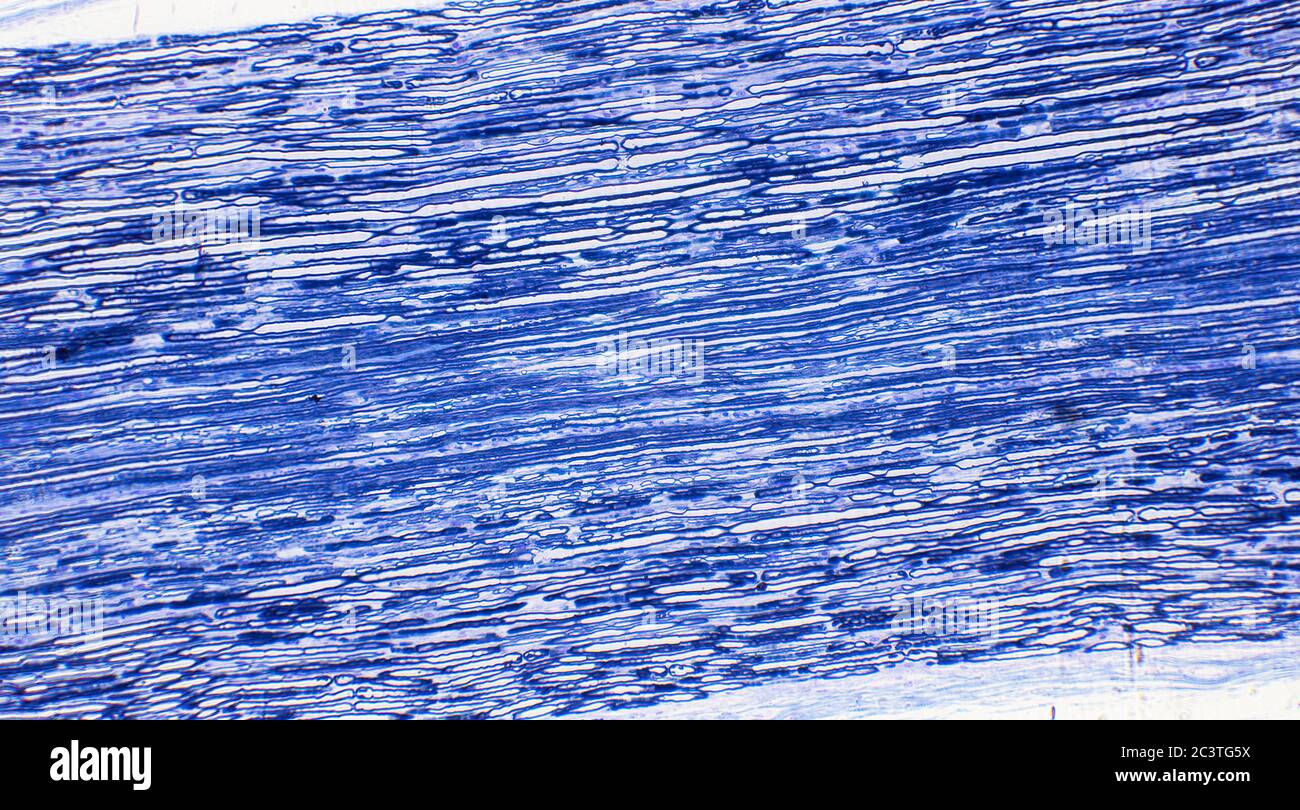

Nerf sciatique mammifère, coupe transversale longitudinale, vue au microscope Banque D'Imageshttps://www.alamyimages.fr/image-license-details/?v=1https://www.alamyimages.fr/nerf-sciatique-mammifere-coupe-transversale-longitudinale-vue-au-microscope-image363801246.html

Nerf sciatique mammifère, coupe transversale longitudinale, vue au microscope Banque D'Imageshttps://www.alamyimages.fr/image-license-details/?v=1https://www.alamyimages.fr/nerf-sciatique-mammifere-coupe-transversale-longitudinale-vue-au-microscope-image363801246.htmlRM2C3TG5J–Nerf sciatique mammifère, coupe transversale longitudinale, vue au microscope

Nerf sciatique mammifère, coupe transversale longitudinale, vue au microscope Banque D'Imageshttps://www.alamyimages.fr/image-license-details/?v=1https://www.alamyimages.fr/nerf-sciatique-mammifere-coupe-transversale-longitudinale-vue-au-microscope-image363801254.html

Nerf sciatique mammifère, coupe transversale longitudinale, vue au microscope Banque D'Imageshttps://www.alamyimages.fr/image-license-details/?v=1https://www.alamyimages.fr/nerf-sciatique-mammifere-coupe-transversale-longitudinale-vue-au-microscope-image363801254.htmlRM2C3TG5X–Nerf sciatique mammifère, coupe transversale longitudinale, vue au microscope